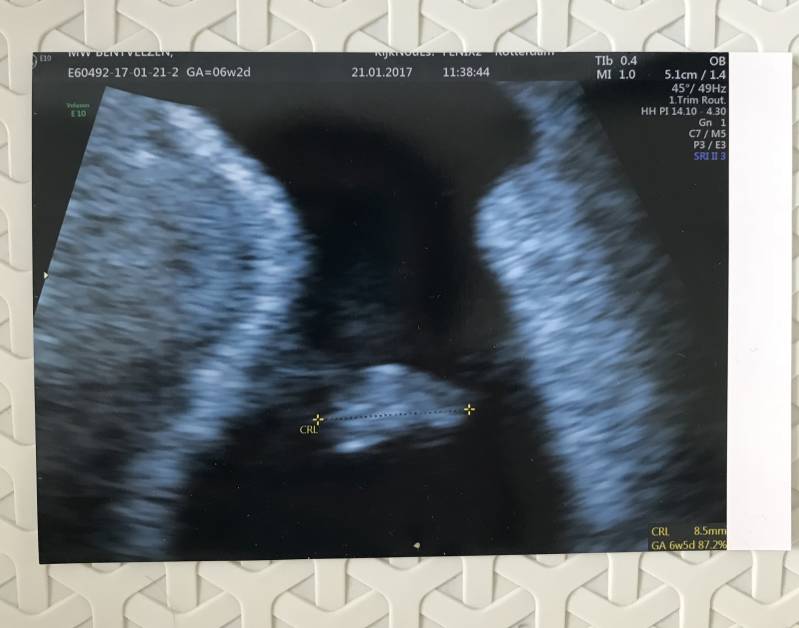

Op 21 Januari hadden we dan eindelijk de eerste echo! De afspraak was in echopraktijk Kijk nou es!* in Rotterdam. Wij hebben voor deze locatie gekozen omdat ze daar al vanaf 6wk een echo inplanden, en wij wilden natuurlijk zo snel mogelijk ons kindje zien. Kotsmisselijk kwam ik daar aan, ook door de zenuwen, en we moesten even wachten voordat we geholpen werden. Toen ik eenmaal op de onderzoeksbank lag en de echo werd gemaakt, zagen wij daar een piepklein balletje, en als je goed keek zag je zelfs het hartje kloppen! Het zag er allemaal goed uit, en wij gingen zielsgelukkig weer naar huis. Het was een kindje! Een kloppend hartje! Toen konden we gaan bedenken hoe wij dit iedereen gingen vertellen, en wanneer!